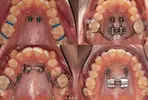

Diş Çapraşıklığı

Diş Çene ve Yüz Bölgesi Gelişim Yetersizlikleri